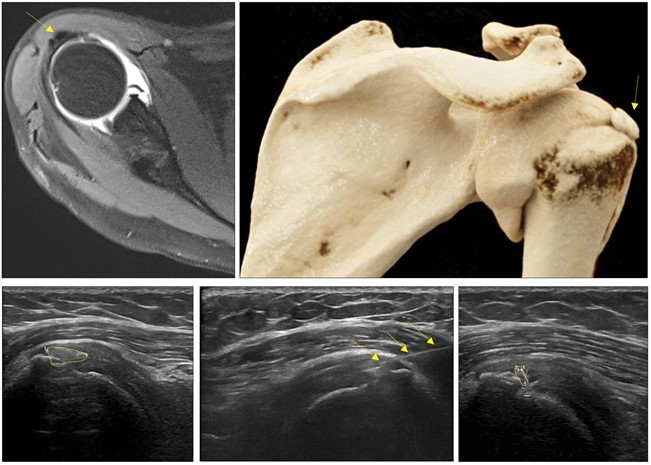

Reconstrucción de un tratamiento que muestra una tendinopatía calcificante de supraespinoso (imágenes superiores de una resonancia magnética) y como el lavado de calcio guiado por ecografía permite disminuir el tamaño de la calcificación (imágenes inferiores de una ecografía).

La unidad de intervencionismo de lesiones del sistema musculoesquelético (SME) controlada por ultrasonidos desarrolla diferentes procedimientos, entre ellos el lavado percutáneo de tendinitis calcificante. Esta técnica se aplica en el manejo de la tendinosis calcificante del manguito rotador, que es una causa importante de dolor frente a la que el tratamiento conservador es menos eficaz y la cirugía, requiere un prolongado periodo de incapacidad postquirúrgica y no está exenta de complicaciones. Frente a estas dificultades, Resona aplica una alternativa sencilla, menos costosa y eficaz, como es la extracción de las calcificaciones mediante su aspiración percutánea. El procedimiento se efectúa bajo control de ultrasonidos que garantiza una localización más exacta de las lesiones.

El paciente candidato a este procedimiento es aquel con tendinitis calcificantes sintomática y con un calcio de al menos 5 mm visible en radiografía y ecografía. En dos metaanálisis comparando distintos tratamientos, incluyendo ondas de choque, el lavado de calcio percutáneo con inyección de corticoides en la bursa se sitúa como la prueba de elección no quirúrgica para el tratamiento de la tendinopatía calcificante. Varios estudios demuestran mejores resultados respecto a la disminución/desaparición del calcio y en mejoría de los síntomas 1 aplicando esta técnica.